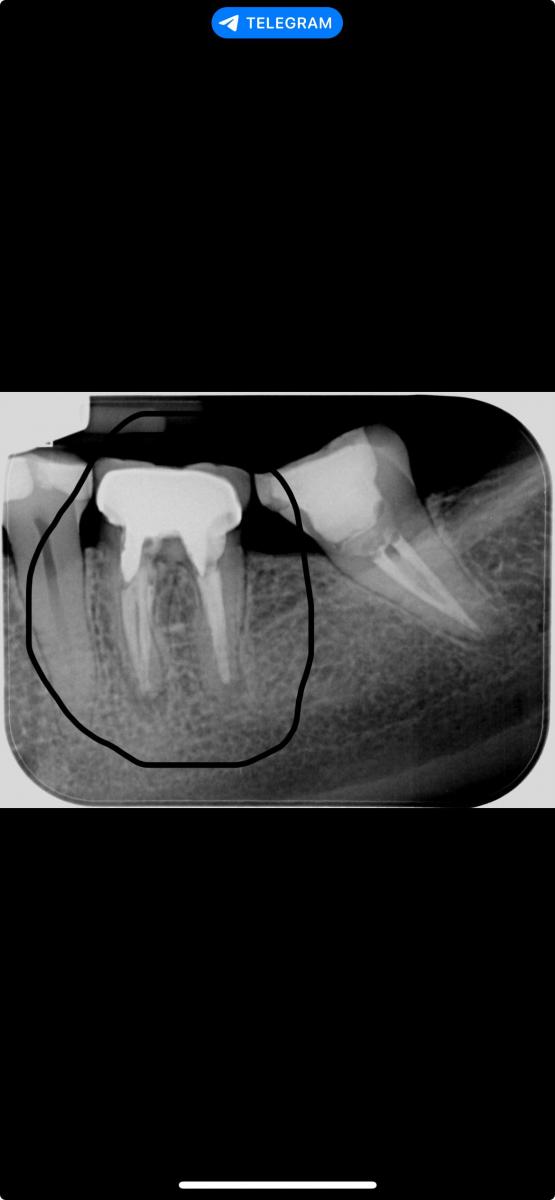

Здравствуйте! Болит шестерка снизу при постукивании и сам по себе, монотонно пульсирует.

Уже нечего перелечивать! Проблема не в кистах, а в том, что зуб рассыпался и держится на честном слове!

Zinasaa, коронковая часть отломана - чётко видна линия перелома, под ней - воспаление поэтому и боль!